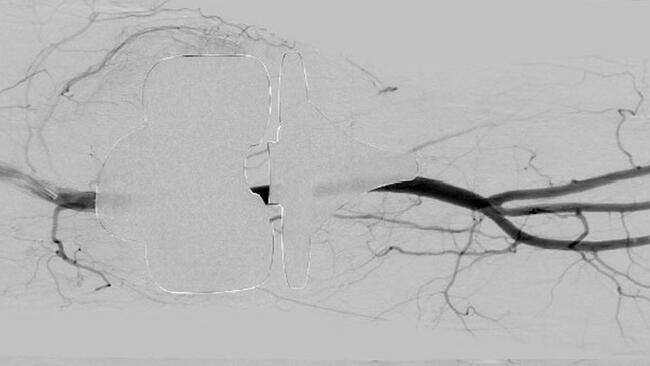

Oblique imaging may be necessary to identify the origin of the genicular arteries, particularly in the postoperative setting. Angiography will aid in identifying areas of synovial blush with the joint space. This finding is largely thought to be representative of synovial hyperemia secondary to angiogenesis. The 5F base catheter should be advanced as close as possible to the ostium of the desired genicular branch for stability as the microcatheter system is deployed. Standard microcatheter systems (2.4F to 2.8F) may not be successful for smaller tortuous vessels, and a smaller system may need to be utilized. For hemarthrosis, embolization is performed using particles ranging from 300 to 500 µm.13 In the setting of GAE treatment for OA, studies have been performed using much smaller particles, typically ranging from 100 to 300 µm. Larger embolic particles may be associated with reduced nontargeted embolization, such as cutaneous branches and those supplying ligamentous components of the joint.14 The endpoint of embolization is pruning of the neovascularity with preservation of the normal genicular artery.

See Figure 1 and Figure 2 for cases of knee OA treated with GAE.